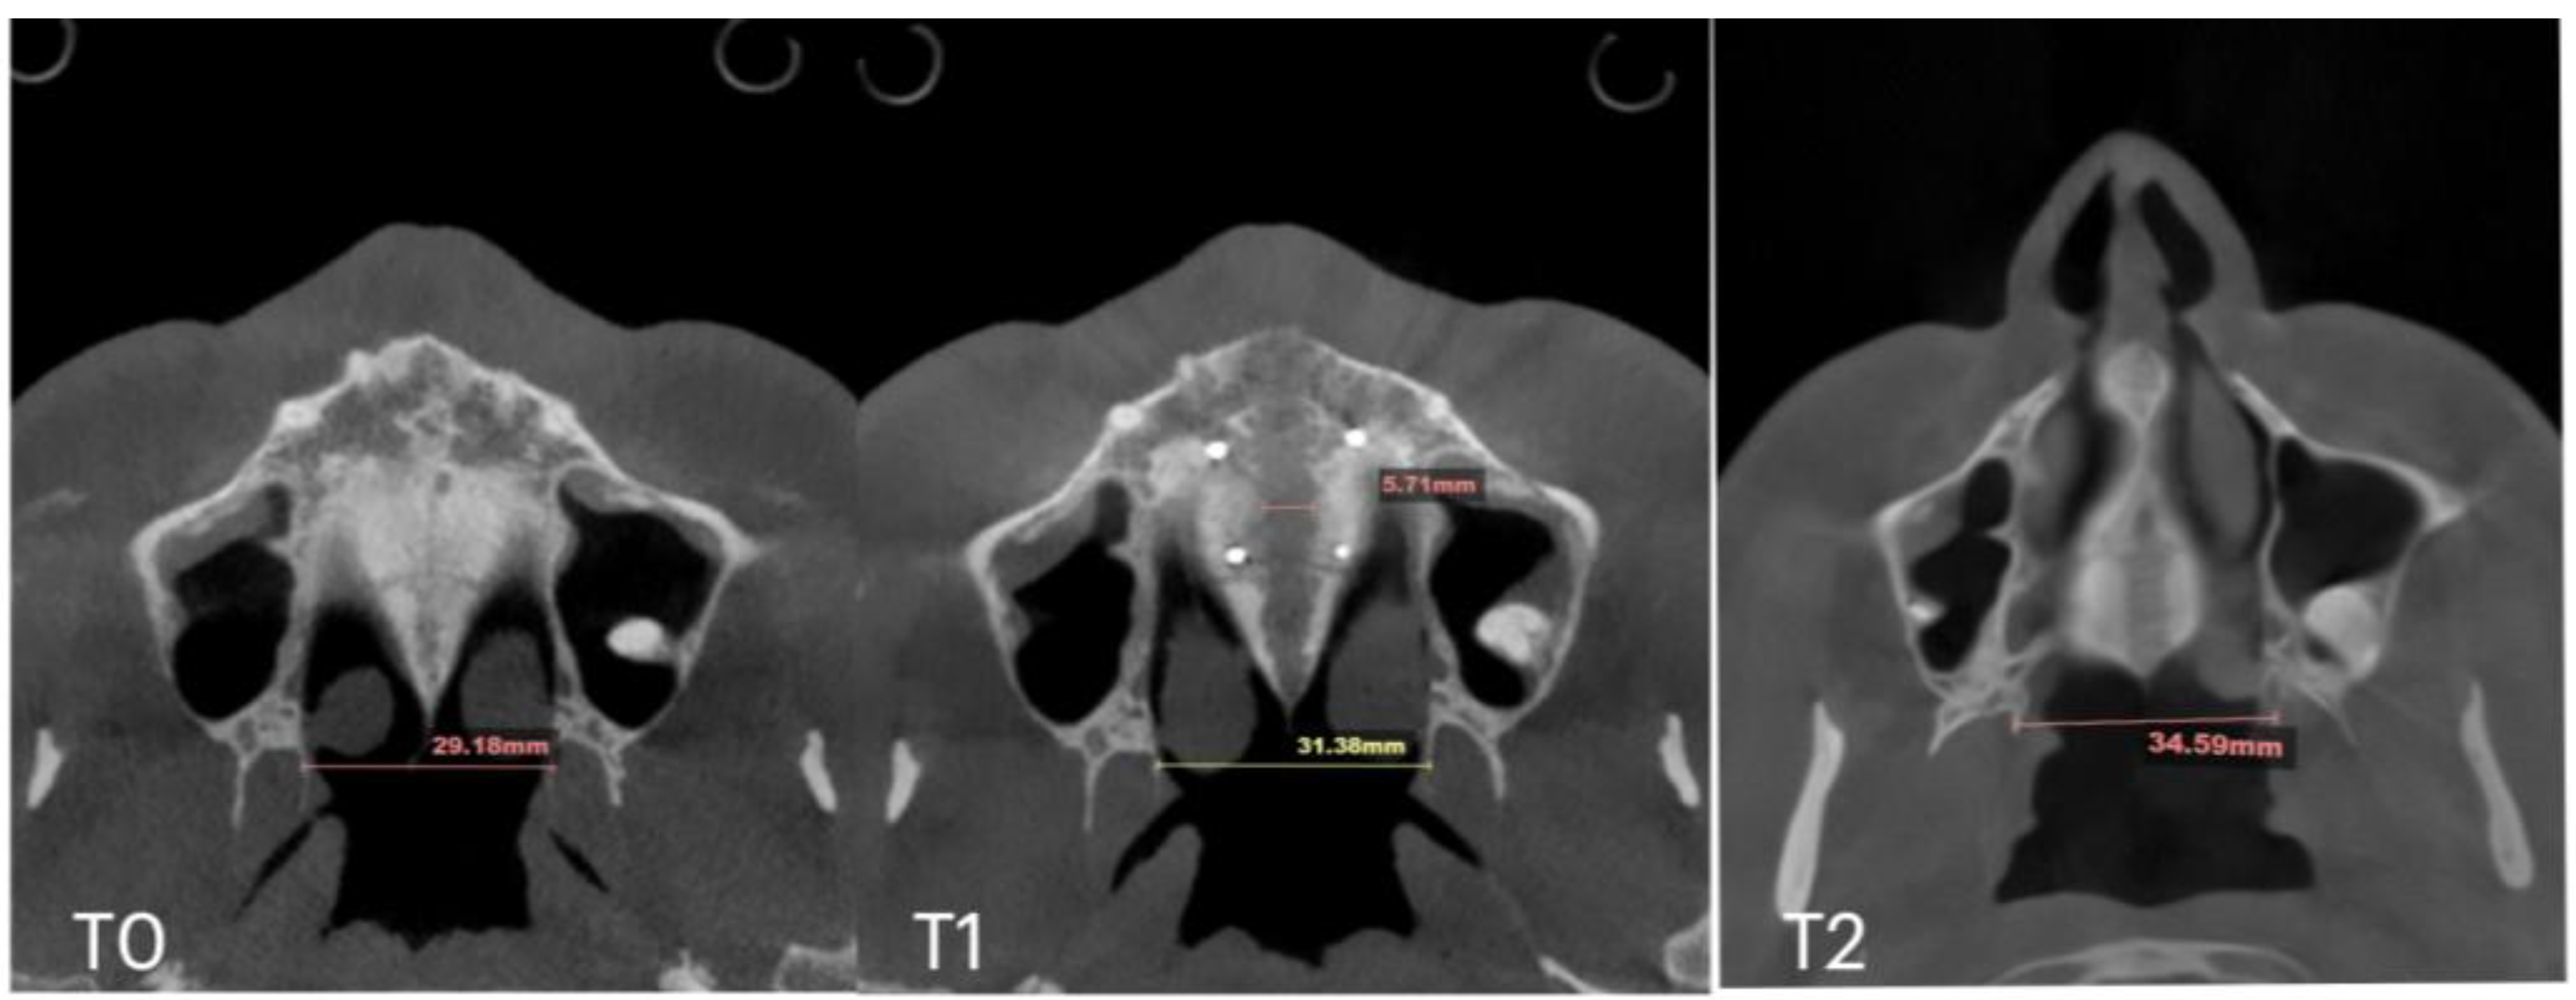

| Case B | 30.61 | 34.41 | 34.97 | 59.73 | 63.47 | 60.56 | 31.79 | 34.6 | 35.35 | 29.18 | 31.38 | 34.59 | 5.7 |